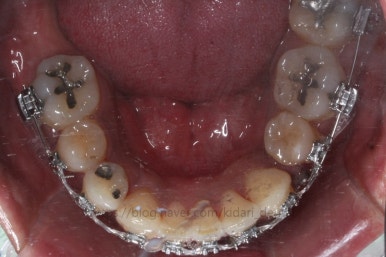

드디어 치료 종료시의 모습입니다. 2년 4개월 걸렸네요.

앞니 안쪽에는 유지철사를 붙여주었고요. 임플란트가 필요한 부위랑 맞닿은 부분은 치열이 움직이지 않도록 철사로 잡아주었어요.(오른쪽 어금니 부위)

삐뚤었던 치아들이 가지런해졌습니다.

왼쪽 송곳니를 발치했지만 별로 표시가 안나게 마무리를 했습니다.

많이 썩은 치아들은 다 뽑았고, 틈새도 다 다물어졌습니다.

원래 패여 있던 부위는 완벽하게 만들기는 힘들지만 앞으로 관리를 잘해주시면 이 모습 그대로 오래 사용하실 수 있으실거에요.